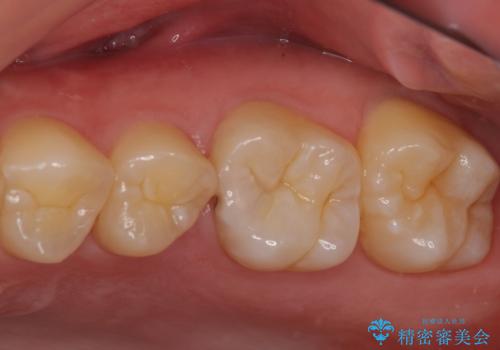

見た目、噛み合わせともに満足していただけました。

ラバーダム防湿を行い、セラミックの接着をすることで、唾液や血液などの接着阻害因子を排除することができます。